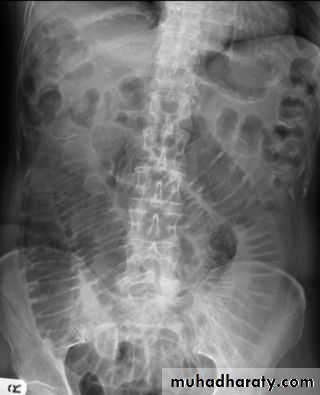

Dilatation of the bowel

Dilatation of the bowel is the cardinal plain film sign of intestinal obstruction

If the bowel is dilated it is important to try and decide which portion is involved

The valvulae conniventes (seen in proximal and mid small bowel) are always closer together than the colonic haustra and cross the width of the bowel , often giving "stack of coins" appearance

The colonic haustra ,which usually form incomplete bands across the colonic gas shadows, are always present in the ascending and transverse colon, but may be absent distal to the splenic flexure

Small bowel obstruction

Large bowel obstruction

Valvulae conniventes

Present

Absent

Number of loops

Many

Few

Distribution of loops

Central

Peripheral

Haustra

Diameter

3 – 5 cm

More than 5 cm

Radius of curvature

Small

Large

Fecal material